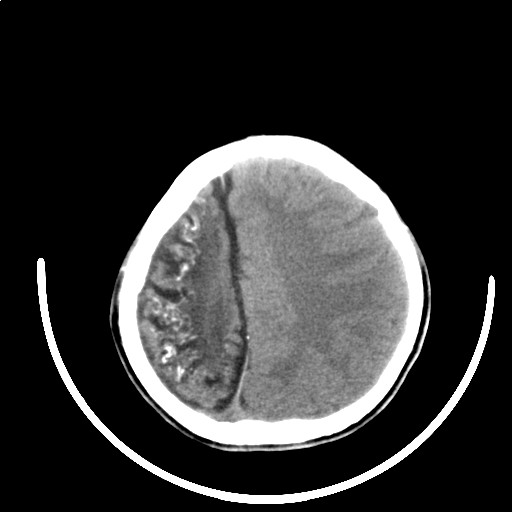

标题: PED3416:F,12Y,智力下降,学习成绩差,8个月时发过高烧。

右侧半球萎缩,软化,多量脑回样钙化,考虑颅面血管瘤病,建议dsa检查

右侧半球萎缩,软化,多量脑回样钙化,同侧颅盖板障增宽,考虑颅面血管瘤病,建议dsa检查与化脓性脑膜炎后遗改变鉴别。